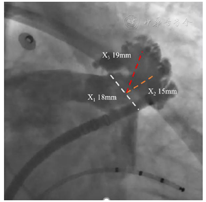

为进一步行评估左心耳结构特点,因此为患者进一步安排CT评估,CT提示左心耳内未见血栓,三维重建后左心耳呈低位,反鸡翅型,开口椭圆形,最短径17.3mm,最长径21.7mm,三维深度19.1mm,二维深度18.0mm,内部梳状肌较为发达。(图1)

阐述该病例处理难点及进一步策略制定:由TEE及CT评估结果可知,该患者左心耳特点①低位心耳,开口较小;②反鸡翅型,且发出转折较早,转折前深度欠缺;因此该患者左心耳封堵难度较大。通过进一步分析左心耳CT后发现,该患者左心耳除主叶外尚有上中下三个分叶,但中下分叶较小且深度较浅,预计输送鞘进入难度及风险均较大,而上叶较宽且深度较中下两个分叶更合适,因此在封堵策略上,考虑采用24mmWatchman封堵器,首选上叶进行尝试(图2)。

穿刺成功先行房颤射频消融治疗,消融完成后更换左心耳封堵鞘,以猪尾导管保护于RAO30° CAU25°造影,左心耳形态充分暴露,可以观察到心耳属于反鸡翅形状。内部梳状肌较发达,深度较浅。DSA测量开口18mm,深度19mm,与CT测量结果类似,考虑选择24mm watchman封堵器,首选X3轴向进行封堵。术中在猪尾导管的保护下,逆时针旋转输送鞘,尽量将输送鞘送入上叶。稳定输送系统,体外预借2mm深度,送入封堵伞,逆时针旋转稳定输送鞘,术中缓慢释放封堵伞,释放后稳定5分钟后造影提示封堵完全,上缘轻度露肩,行TEE检查未见残余分流,压缩比测量12.5%~21%(图7,图8),经牵拉测试稳定,符合PASS原则,决定释放封堵器,释放后再次造影提示封堵完全(图9)。术后患者顺利清醒,术后6小时检测无心包积液,加用达比加群110mg 2次/天;术后第五天出院。